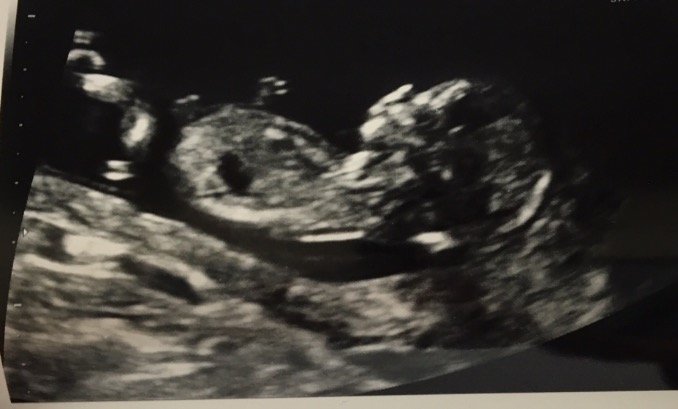

My midwife is so awesome!! After our initial appointment today she pulled out the ultrasound machine so we could have a quick look at our peanut. This baby is super active, would barely hold still long enough for a picture. Our midwife enjoyed it as much as we did. I am measuring 2 days ahead at 11 weeks 4 days, but not enough to move up my due date.

12 plus 5 according to scan. We were 12 plus 2 but gained 3 days. Our first scan. Got to see the baby waving its arms up and down which was so cute. Funny, they all look so similar, but yours is so special when you finally see it. I had to bump my hips up and down to wake baby up too! Got to see it float up and then drift back down.